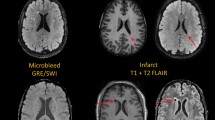

Hypertension causes pathological alterations in cerebral microvessels that damage microvascular structure, network architecture and function, and contribute to the genesis of cerebral microhaemorrhages, lacunar infarcts and white matter injury; these factors are associated with cognitive decline.

Ungvari, Z., Tarantini, S., Kirkpatrick, A. C., Csiszar, A. & Prodan, C. I. Cerebral microhemorrhages: mechanisms, consequences, and prevention. Am. J. Physiol. Heart Circ. Physiol. 312, H1128–H1143 (2017).

Yates, P. A. et al. Cerebral microhemorrhage and brain β-amyloid in aging and Alzheimer disease. Neurology 77, 48–54 (2011).

Petrea, R. E. et al. Mid to late life hypertension trends and cerebral small vessel disease in the framingham heart study. Hypertension 76, 707–714 (2020).

- Lacunar infarcts

Small infarcts (2–20 mm in diameter) in the deep cerebral white matter, basal ganglia, or pons that are presumed to result from the occlusion of a single small perforating artery supplying the subcortical areas of the brain.

- White matter lesions

Areas of abnormal myelination in the brain that are best visualized as hyperintensities on T2-weighted and fluid-attenuated inversion recovery (FLAIR) MRI sequences.